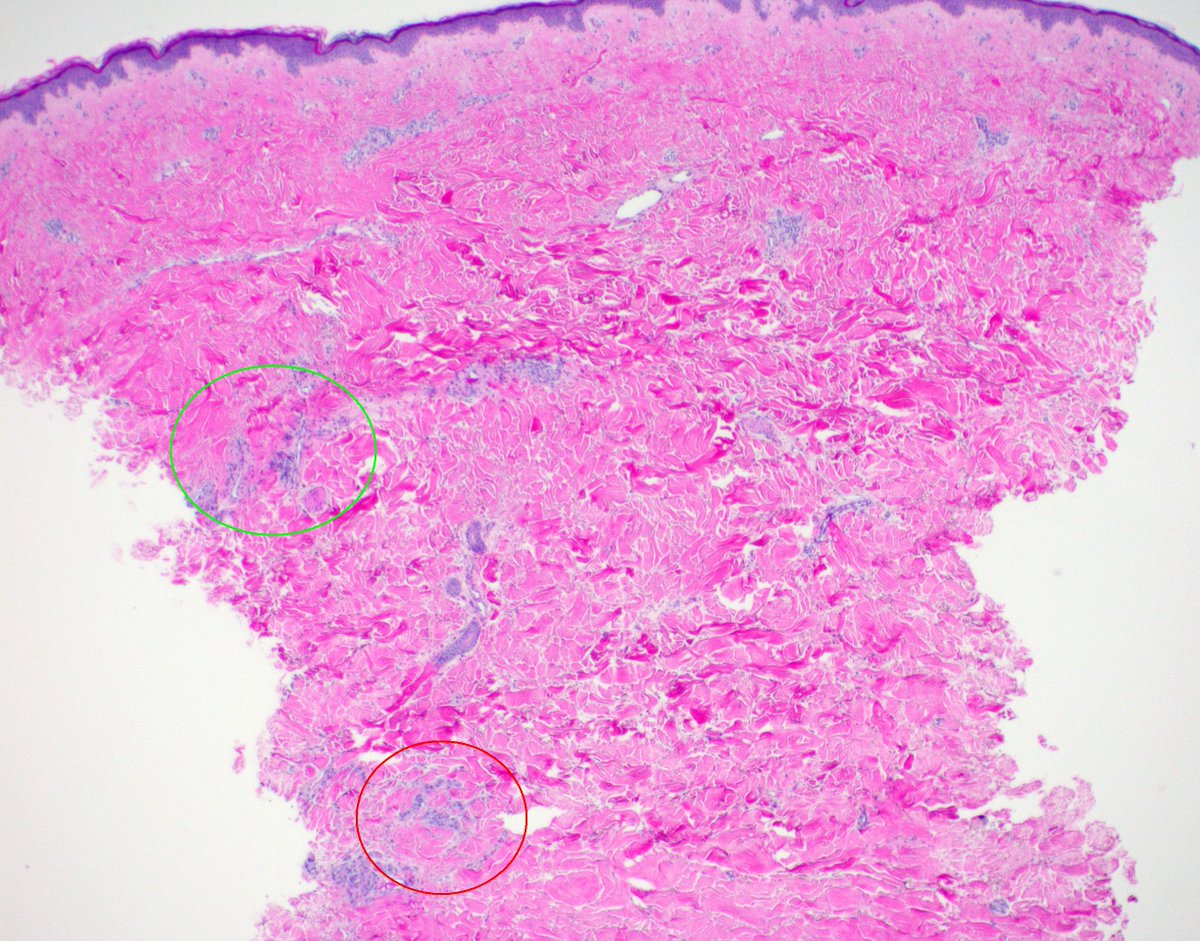

Breast skin biopsy - superficial green circle with urticarial inflammatory reaction suggests all okay, but deeper red circle shows metastatic breast CA. Biopsy size = biopsy accuracy #dermatology #breastcancer